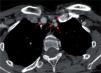

Figura 4.

C3: artérias vertebrais direita e esquerda nos buracos transversários (setas).